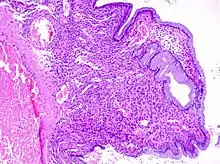

Cervical polyps can be seen during a pelvic examination as red or purple projections from the cervical canal.[4] Diagnosis can be confirmed by a cervical biopsy which will reveal the nature of the cells present.[4]

Cervical polyps are finger-like growths, generally less than 1 cm in diameter.[4][5] They are generally bright red in colour, with a spongy texture.[3] They may be attached to the cervix by a stalk (pedunculated) and occasionally prolapse into the vagina where they can be mistaken for endometrial polyps or submucosal fibroids.[5]